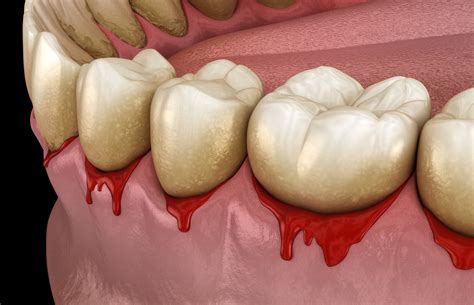

Distinguishing Gingivitis from Periodontitis

It is crucial to understand the progression of gum disease. Gingivitis is the early, reversible stage characterized by red, swollen, and bleeding gums. If left unaddressed, it can advance to periodontitis. In this stage, the infection spreads below the gum line, damaging the bone and supporting structures of your teeth. Once periodontitis sets in, the damage is often irreversible, and professional intervention is mandatory to prevent tooth loss.

⚠️ Note: If your gums bleed randomly and you also experience loose teeth, persistent bad breath, or receding gum lines, consult a dental professional immediately, as these are advanced indicators of periodontal disease.

Bleeding accompanied by metallic taste Potential infection / Periodontitis Schedule professional cleaning